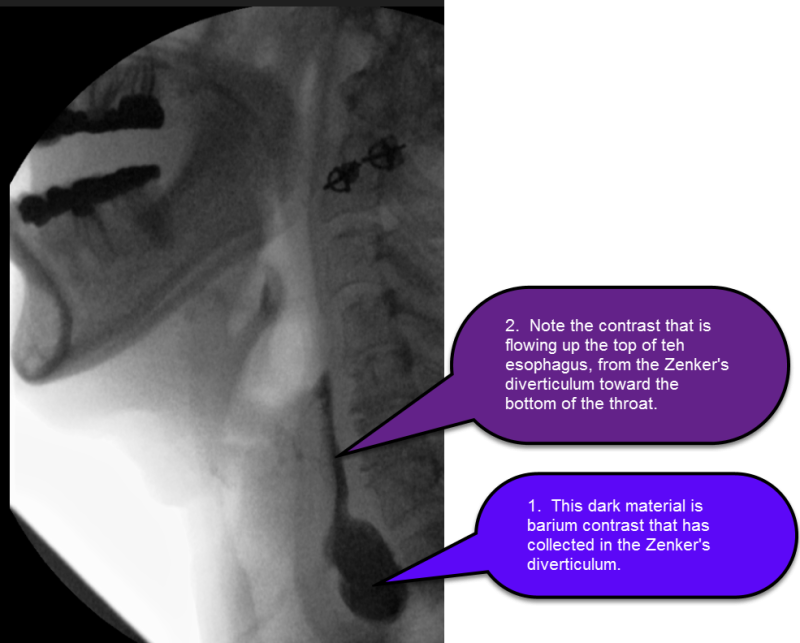

Comparison of esophagogram between Zenker diverticulum (arrow in a) and Mayo Clinic Zenker Diverticulum In zenker's diverticulum, a bulge or pouch forms at the top of the tube that connects the. To diagnose zenker's diverticulum, a healthcare professional, often an ear, nose and throat (ent) specialist, does a physical exam and asks about your. It’s a pouch that forms at the bottom of your throat where your throat connects to your esophagus. Mayo clinic. Mayo Clinic Zenker Diverticulum.